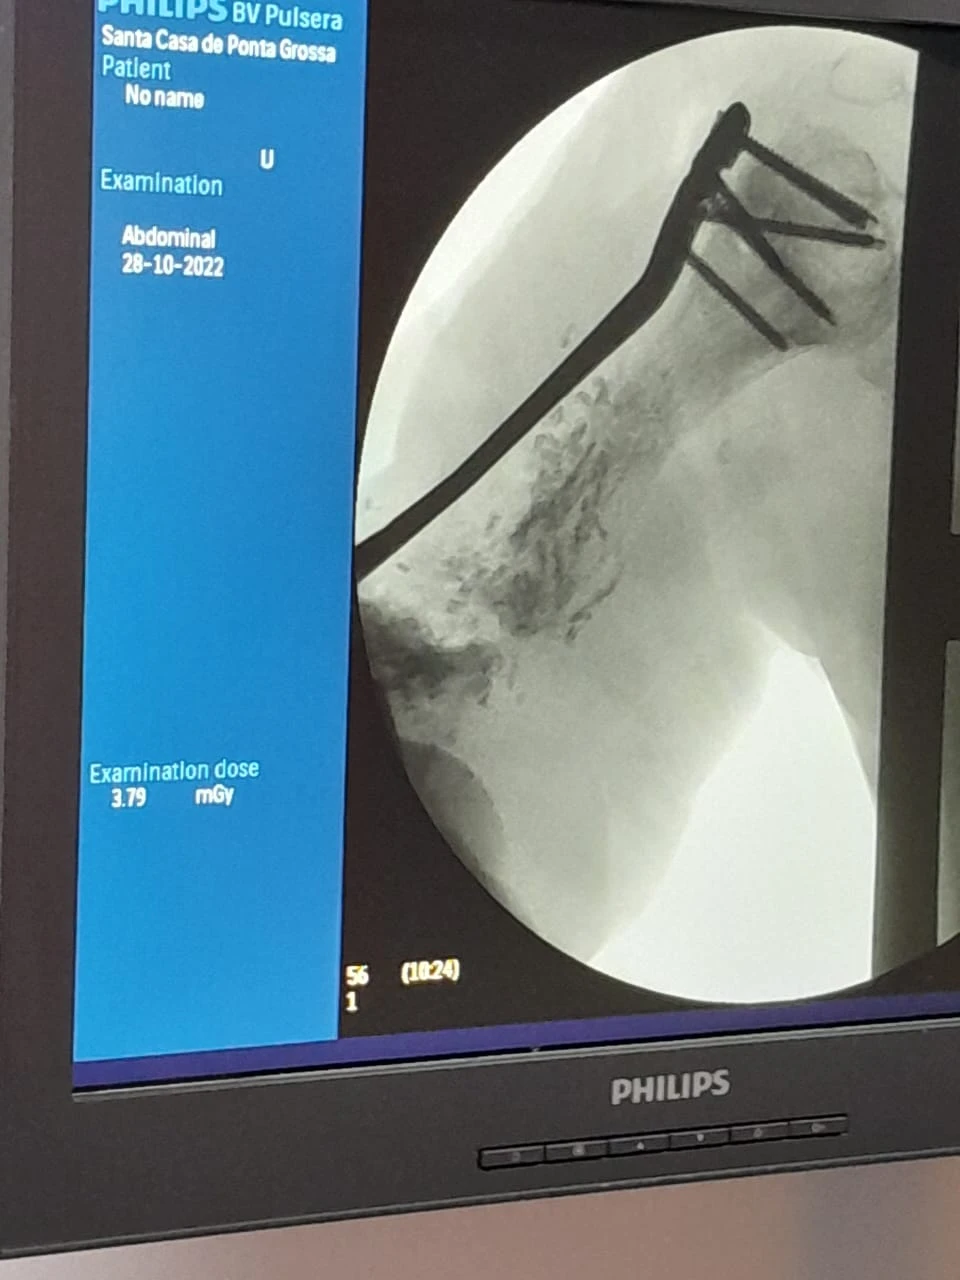

No último dia 28, a equipe de Ortopedia e Traumatologia da Santa Casa de Ponta Grossa realizou um procedimento cirúrgico inédito na região dos Campos Gerais, que consiste na correção de ossos em situações de fraturas. Neste caso, a paciente em questão fraturou o úmero (osso superior do braço), passou por diversas cirurgias em outras instituições, porém sem obter sucesso. O cirurgião Dr Carlos Miers explica a dificuldade para a realização do procedimento: “a cada cirurgia realizada a quantidade de osso disponível no braço era menor, e quando a paciente chegou até mim ela já tinha o úmero direito muito menor que o esquerdo, e com um defeito ósseo grande." A primeira etapa do tratamento consistiu em tratar a infecção, após isso foi necessário fazer um transporte ósseo com fixador externo, utilizado pela paciente durante 2 anos. Em seguida foi necessário estabilizar e fixar o úmero da parte superior até a inferior, porém não havia placa/haste disponível no mercado que supria a necessidade desta paciente “aí que começa a singularidade deste procedimento, nós em parceria com a empresa Neoortho, desenhamos e desenvolvemos uma placa personalizada especifica para a anatomia desta paciente”, explica o profissional. O projeto de personalização da placa foi realizado utilizando tecnologia de ponta através e modelos computacionais extraídos de tomografia, simulações mecânicas em elementos finitos para garantir que o material não iria falhar durante o tratamento: “após diversos testes chegou-se a versão final da placa que foi instalada na paciente durante a cirurgia”, complementa o Dr Carlos. Participaram da cirurgia os profissionais Dr Carlos Miers e o Dr Rodrigo Favaro, o procedimento foi realizado no centro cirúrgico da Santa Casa, durou 4 horas e foi um sucesso. A Instituição que é referência para 28 municípios vem traçando estratégias para cumprir sua missão de acolher e tratar o paciente respeitando sua individualidade, proporcionando uma experiência em saúde com ética, segurança, tecnologia e resolutividade. [gallery size="medium" ids="137648,137649,137650"]